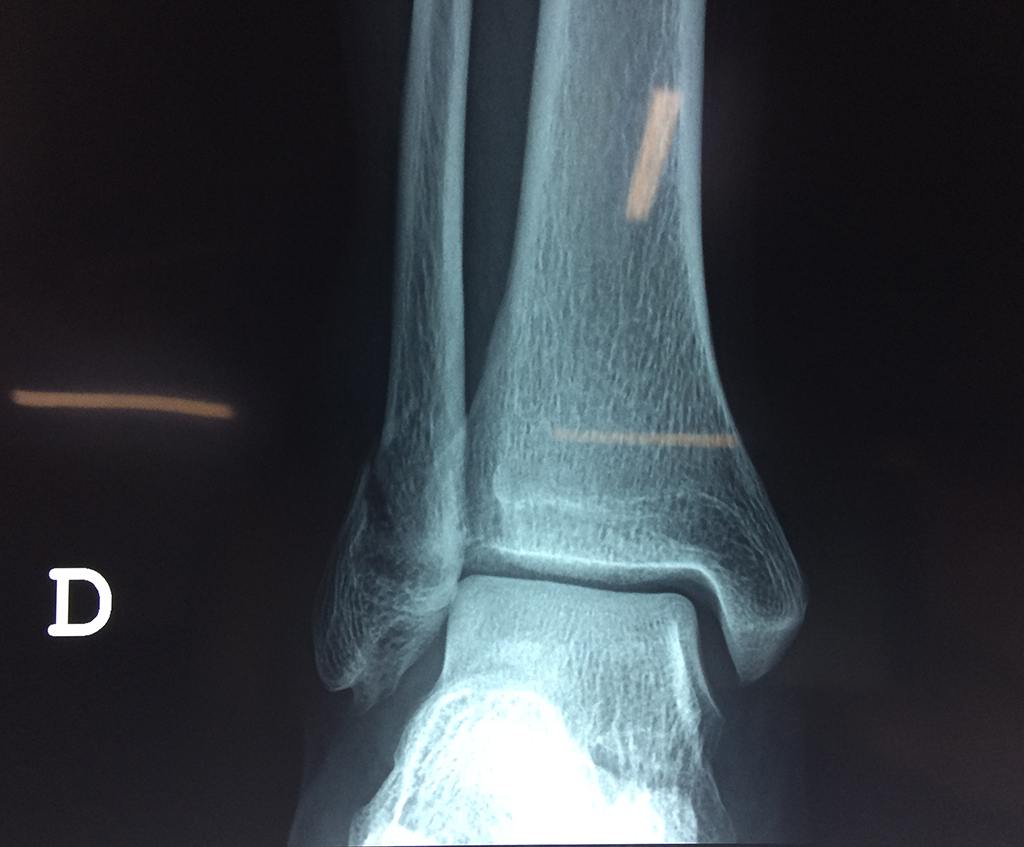

Una fractura de tobillo es la rotura de uno o más de los huesos del tobillo. Estas fracturas pueden ser:

- Parciales (el hueso está sólo parcialmente fisurado, no del todo).

- Completas (el hueso está perforado y está en 2 partes).

- Producirse en uno o ambos lados del tobillo.

Algunas fracturas de tobillo pueden requerir cirugía si:

- Los extremos de los huesos están desalineados entre sí (desplazados).

- La fractura se extiende hasta la articulación del tobillo (fractura intra-articular).